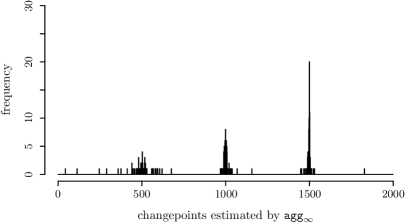

5.4 Real data application

We study the comparative genomic hybridisation (CGH) microarray dataset from Bleakley and Vert (2011), available in the ecp R package (James and Matteson, 2015). CGH is a technique that allows detection of chromosomal copy number abnormality by comparing the fluorescence intensity levels of DNA fragments from a test sample and a reference sample. This dataset contains (test to reference) log intensity ratio measurements of 43 individuals with bladder tumour at 2215 different loci on their genome. The log intensity ratios for the first ten individuals are plotted in Figure 5. While some of the copy number variations are specific to one individual, some copy number abnormality regions (e.g. between loci 2044 and 2143) are shared across several different individuals and are more likely to be disease-related. The inspect algorithm aggregates the changes present in different individuals and estimates the start and end points of copy number changes. Due to the large number of individual-specific copy number changes and the presence of measurement outliers, direct application of inspect with the default threshold level identifies 254 changepoints. However, practitioners can use the associated score to identify the most significant changes. The 30 most significant identified changepoints are plotted as red dashed lines in Figure 5.